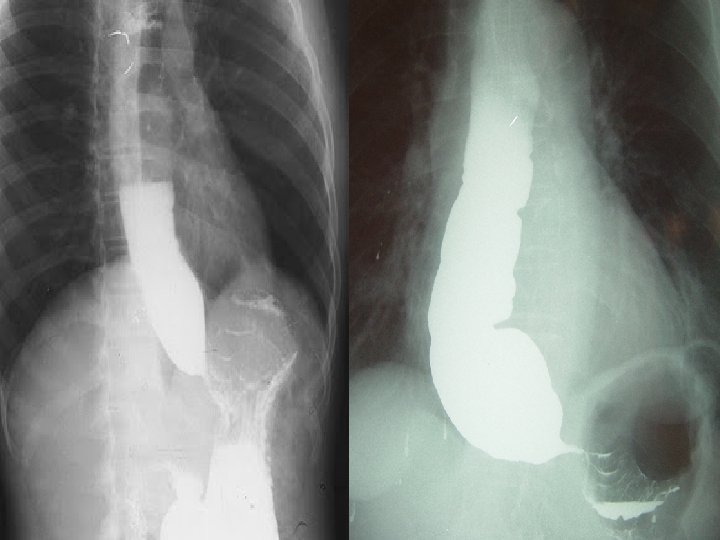

OESOPHAGEAL PERISTALSIS

Primary Oesophageal peristalsisØ It is the continuation of the peristaltic wave that is produced in the pharynx by the contraction of the superior pharyngeal constrictor Ø Its function is to propel the food through the esophagus to the stomach Ø The vagus controls the esophageal peristalsis through the myentric plexus

Oesophageal stage Ø Diffuse spasm of the esophagus Ø Carcinoma of the esophagus Ø Achalasia cardia Ø GERD- Heart burn